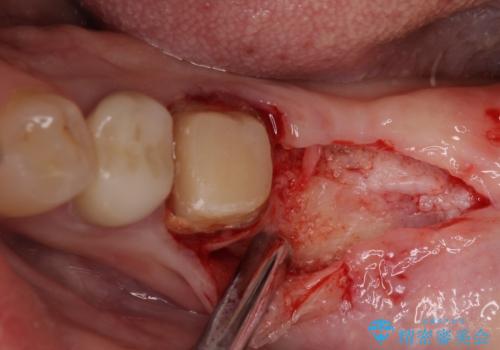

インプラント埋入にあたり、歯槽骨での炎症が広範囲であったことから、事前に骨造成を行いました。

歯槽骨の高さや幅を回復することができ、望ましい位置にインプラントを埋入することができました。